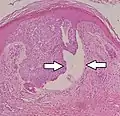

Morpheaform basal-cell carcinoma (also known as "cicatricial basal-cell carcinoma", and "morphoeic basal-cell carcinoma") | Narrow strands and nests of basaloid cells, surrounded by dense sclerotic stroma.[31] | Aggressive[28]: 748 [29]: 647 | ![]() |